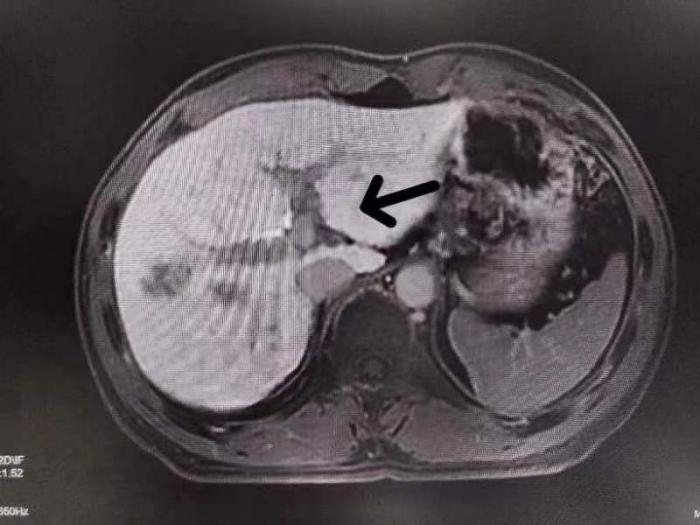

正常组织为白色,病变呈现黑色 | 肝胆期,胆管清晰可见 |

普美显增强MRI检查具有良好的时间、空间和软组织分辨率、无电离辐射、大视野及多平面成像,能够对肝脏形态、功能、血流灌注、组织学特征进行全方位检查。且与普通造影剂不同的是,普美显可通过胆道及肾脏双重排泄,对身体的损害减少。自普美显应用于临床,肝脏结节的病灶检出率及定性诊断的正确性得到大大提高。